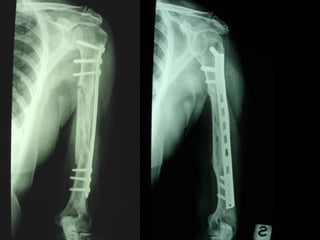

Dal Gennaio 2000 al Dicembre 2005 27 placche LISS di femore

INDICAZIONI COMUNI Fratture sovracondiloidee Fratture intercondiliodee Fratture diafisarie distali PARTICOLARI Fratture con grave osteoporosi Fratture periprotesiche

VANTAGGI CHIRURGIA MININVASIVA Mini Open Inserimento della placca sottocutaneo per scivolamento Viti percutanee Preservazione dei tessuti molli Ridotto danno vascolare Rapida ripresa funzionale

F, 68 y

LISS  NCB

NCB

Conclusioni Riduzione  anatomica Minimo trauma chirurgico Corretto equilibrio fra elasticità e stabilità Precoce mobilizzazione